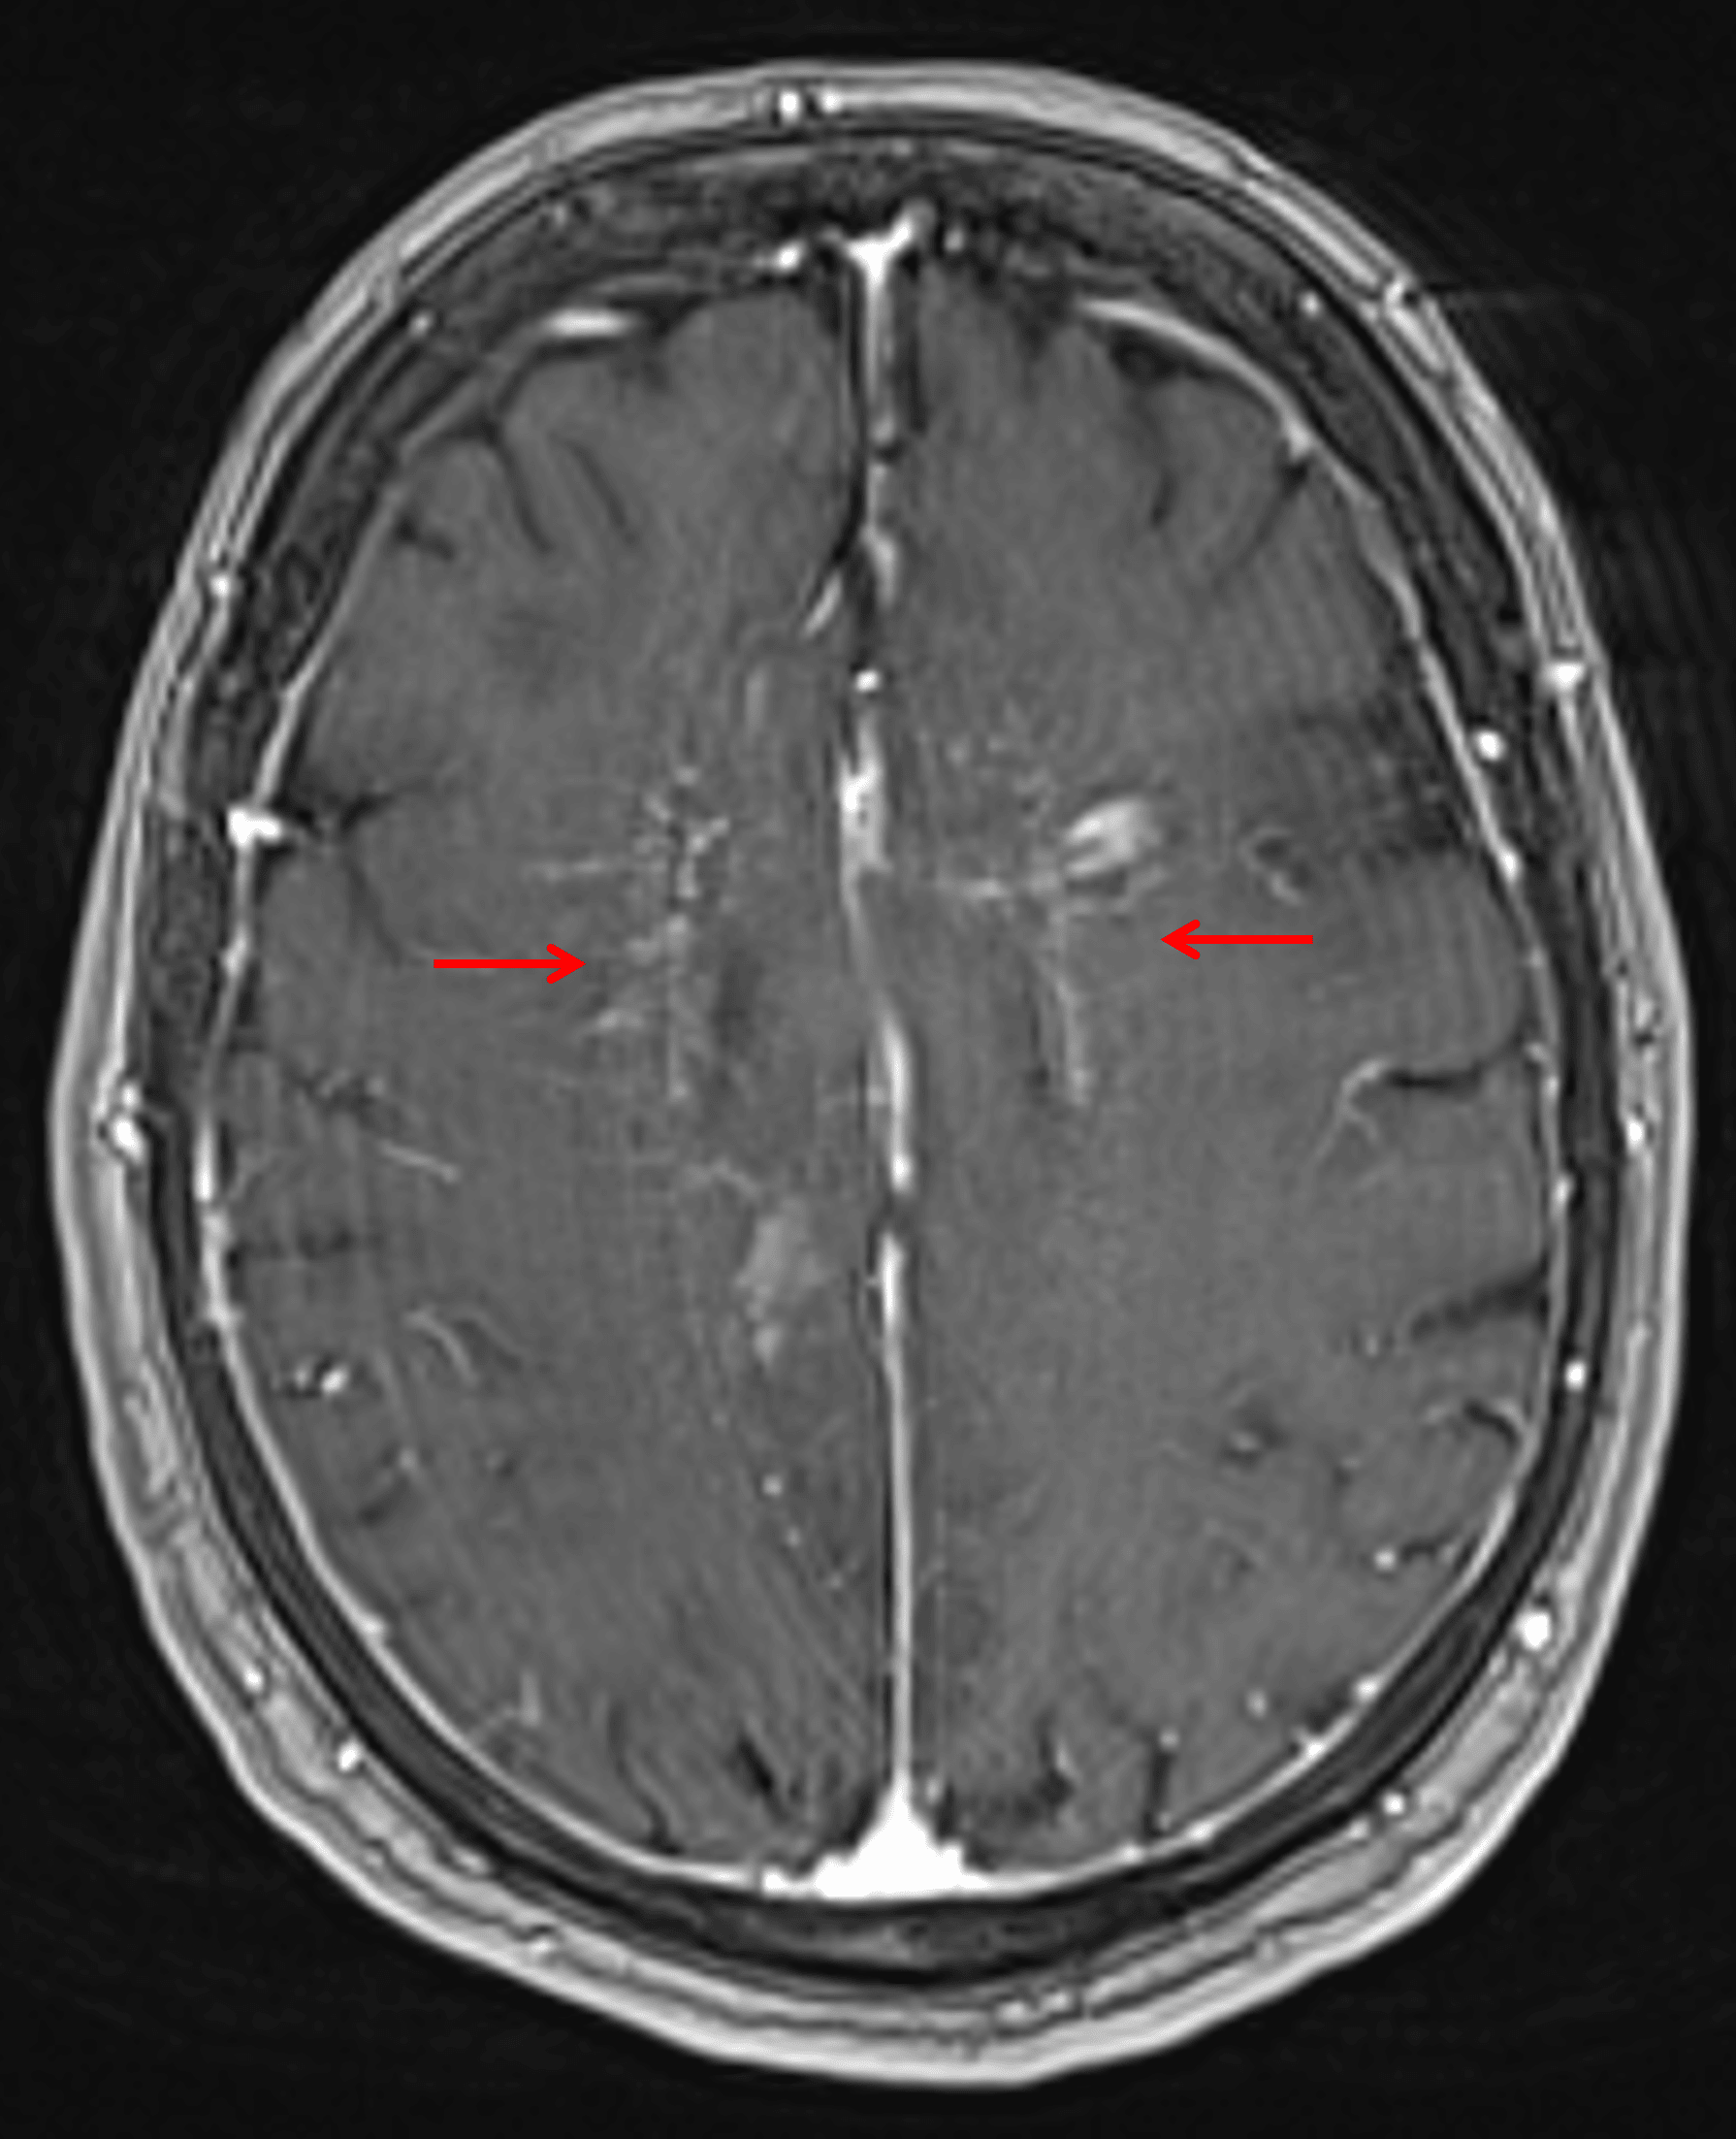

- Relatively symmetric T2/FLAIR signal hyperintensity most pronounced in the supratentorial deep gray nuclei and deep white matter, including the internal capsules and corpus callosum, with associated curvilinear and nodular enhancement in a perivascular distribution

Curvilinear and nodular enhancement tracking along perivascular spaces in the bilateral cerebral white matter (red arrows) in this patient with intravascular lymphoma.